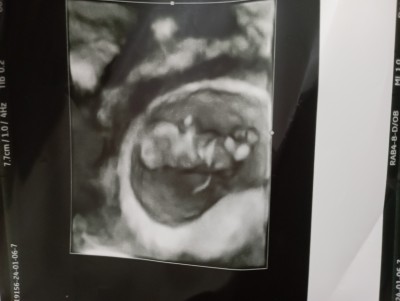

Ultrason görüntüsüne göre cinsiyet tahmini yapabilen var mı?

Gebelik haftası 10 hafta 4 günluk

%51 ihtimalle erkek dedi doktorum ama net değil tabiki haftaya ikili test için gideceğim o zmana kadar belli olur dedi ama ben meraktan bakınıyorum işte .

Erkek kesinlikle canımm belli oluyor bak ortasına